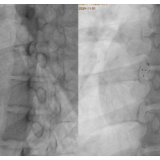

手术在局部麻醉下进行,术中同步运用DSA与超声双重影像引导。团队凭借丰富经验,精准释放封堵器,术后超声提示封堵器位置良好,无残余分流。